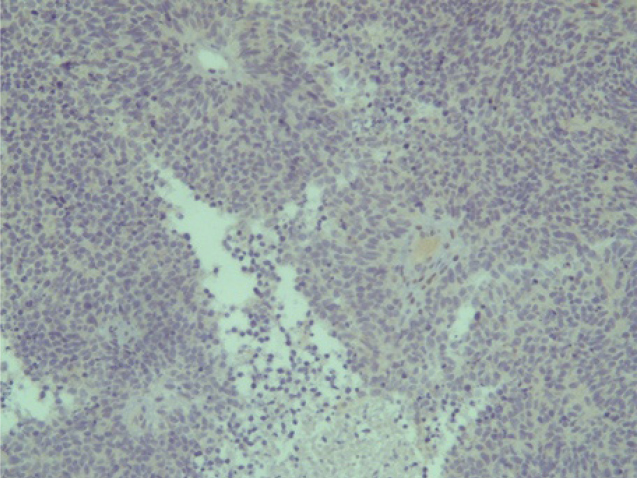

Опухоль с одинаковой частотой локализовалась в правой и левой половинах носа. Но из-за близости соседних анатомических структур и особенностей местнодеструирующего роста опухоли, у двух пациентов первичный очаг изначально диагностировали интракраниально (22,2 %), у двух – в верхнечелюстной пазухе (22,2 %), у одного – в носоглотке (11,1 %) и у двух пациентов (22,2 %) из-за степени распространенности процесса было невозможно анатомически точно определить область первичного возникновения опухоли. В таких ситуациях единственным способом верификации морфологической принадлежности злокачественного процесса является гистологическое исследование (рис. 1).

Эстезионейробластома по своей гистологической структуре напоминает лимфосаркому или симпатобластому и представлена комплексами гиперхромных клеток со структурами типа ложных розеток и скудным нейрофибриллярным матриксом, выраженным полиморфизмом [3, 6].

Рис. 1. Ольфакторная нейрогенная опухоль полости носа (эстезионейробластома, клеточный полиморфизм) ×320 (окраска Г-Э)